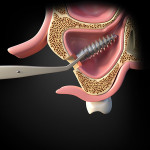

The healing progressed uneventfully. The prosthesis extending from implant Nos. 9 to 15 was supported by four remaining implants (Nos. 9, 11, 13, and 15), which were stable with good peri-implant bone support. It was, therefore, re-cemented after removal of displaced implant No. 14 (Figure 3). The implant and abutment after removal are shown in Figure 4. A 1-year post-surgery OPG confirmed the healed sinus and re-cementation of the prosthesis (Figure 5).

In the present case, the implant was displaced into the sinus approximately 6.5 years after loading, presumably as a result of bone loss due to peri-implantitis. The cement-retained implant restoration, which was loose due to cement washout, was removed, allowing access to and removal of the displaced implant and abutment without causing damage to the prosthesis. However, the cemented restoration, as it was in this case, combined the abutment and implant in one unit, and they, therefore, were displaced as one unit. This displacement could have been caused by overload on the implant when the cement on the implant/abutment separated from the fixed restoration or by cement washout and peri-implantitis-related bone loss loosening the implant. (The authors surmised that if there was no bone loss and only cement washout, the implant may have remained in position as did the others under the fixed splint; moreover, when the implant ultimately was removed from the sinus, there was no evidence of cement on it [Figure 4] or under the fixed restoration.)